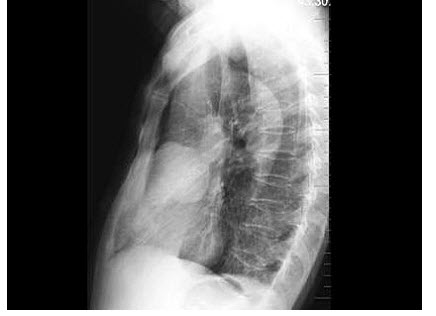

179、单项选择题

女,1岁10个月,右肘部外伤,如图所示,最佳的诊断为()

A.全骺分离

B.肱骨髁上骨折

C.肱骨髁上骨折并肘关节脱位

D.内上髁骨骺损伤

E.内上髁骨骺损伤并肘关节脱位